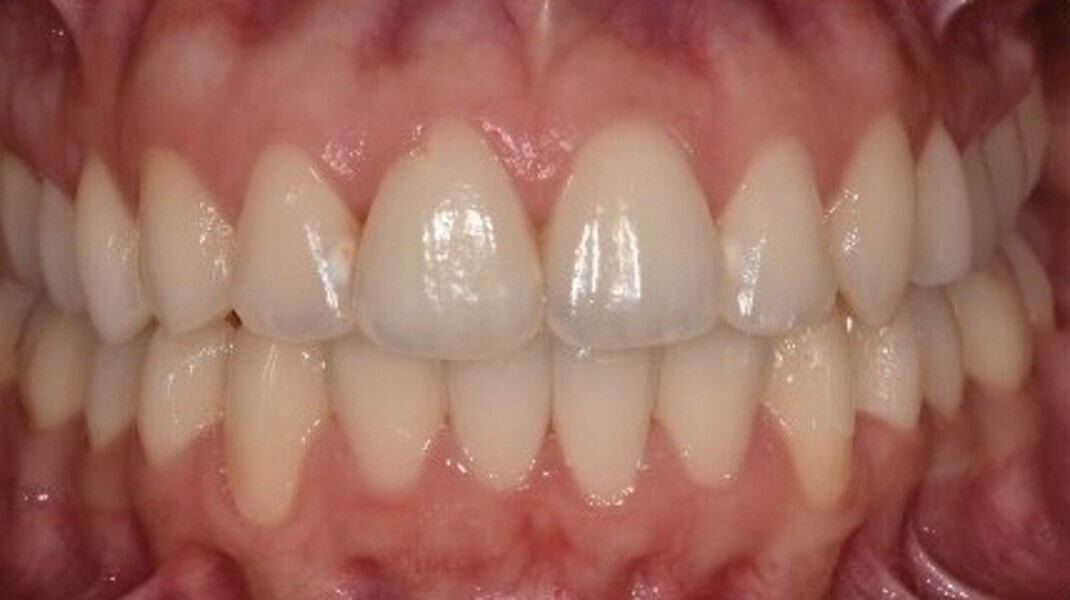

Le motif principal de consultation de la patiente, une jeune femme de 27 ans, est un encombrement dentaire accompagné d’une occlusion mal équilibrée. Danseuse de profession, elle se tracasse énormément au sujet de son apparence lors de ses apparitions publiques si elle entreprend un traitement. L’examen clinique révèle une relation d’Angle de classe I du côté droit et une relation molaire canine de classe II du côté gauche (Fig. 1).

Fig. 1b : Photographie intraorale initiale.

Après une période de onze mois et un nombre total de 66 aligneurs maxillaires et mandibulaires, le traitement est terminé et tous les objectifs sont atteints, à savoir une relation bilatérale de Classe I, une symétrie des arcades et la correction de l’encombrement (Fig. 6).

Fig. 6a : Photographie intraorale finale.